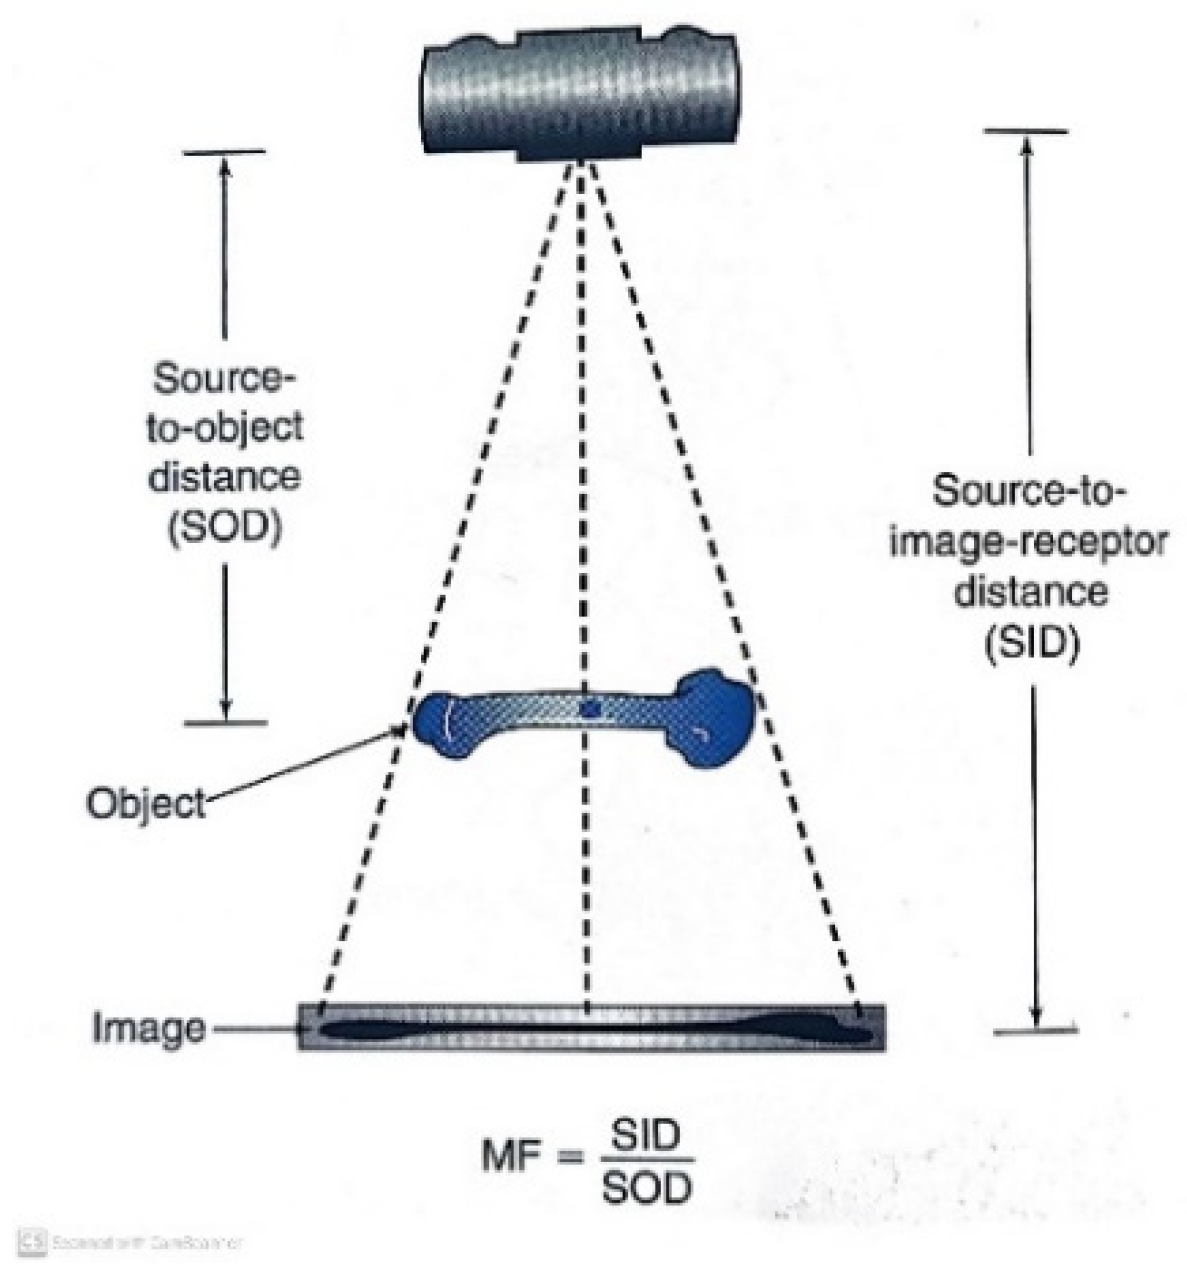

2. Materials and Methods

- IS = Image size

- OS = Object size

- SID = Source to image distance

- SOD = Source to object distance

- OID = Object to image distance

- O%MF = Object % of magnification